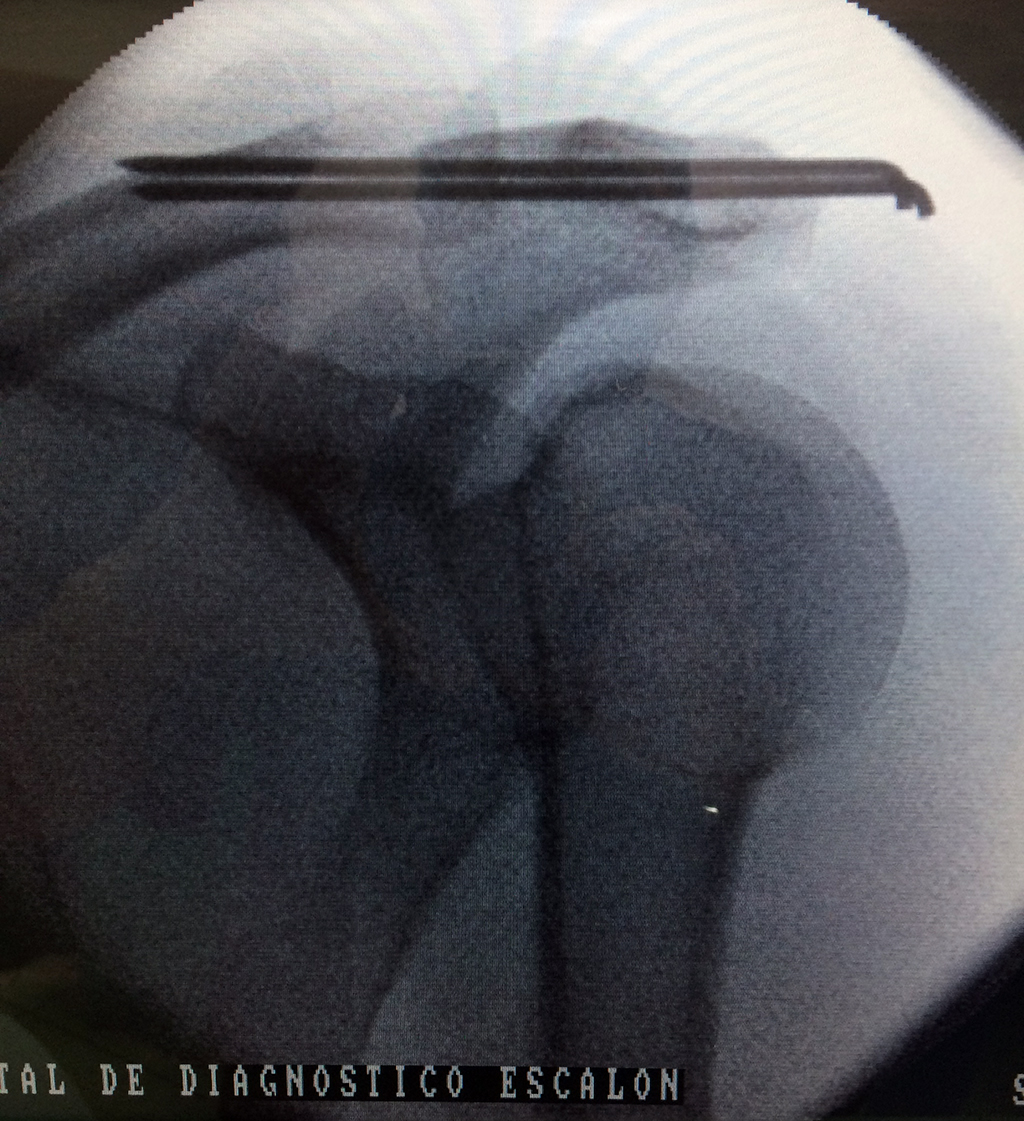

Cirugías de Calcaneo - Clavícula